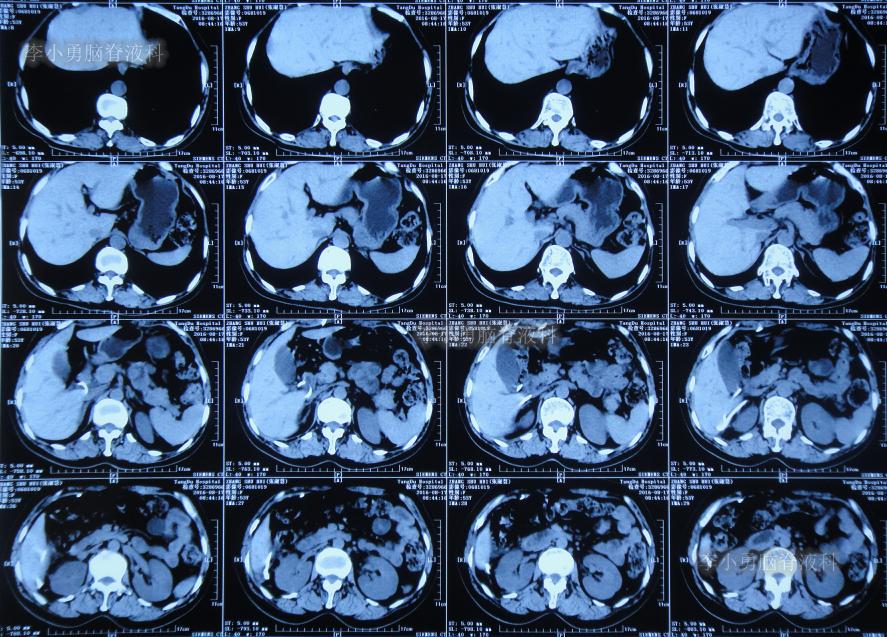

住院次日即2016年8月17日,查腹部CT:仍有腹腔积液( 图-8 )。

图-8: 2016年8月17日腹部CT